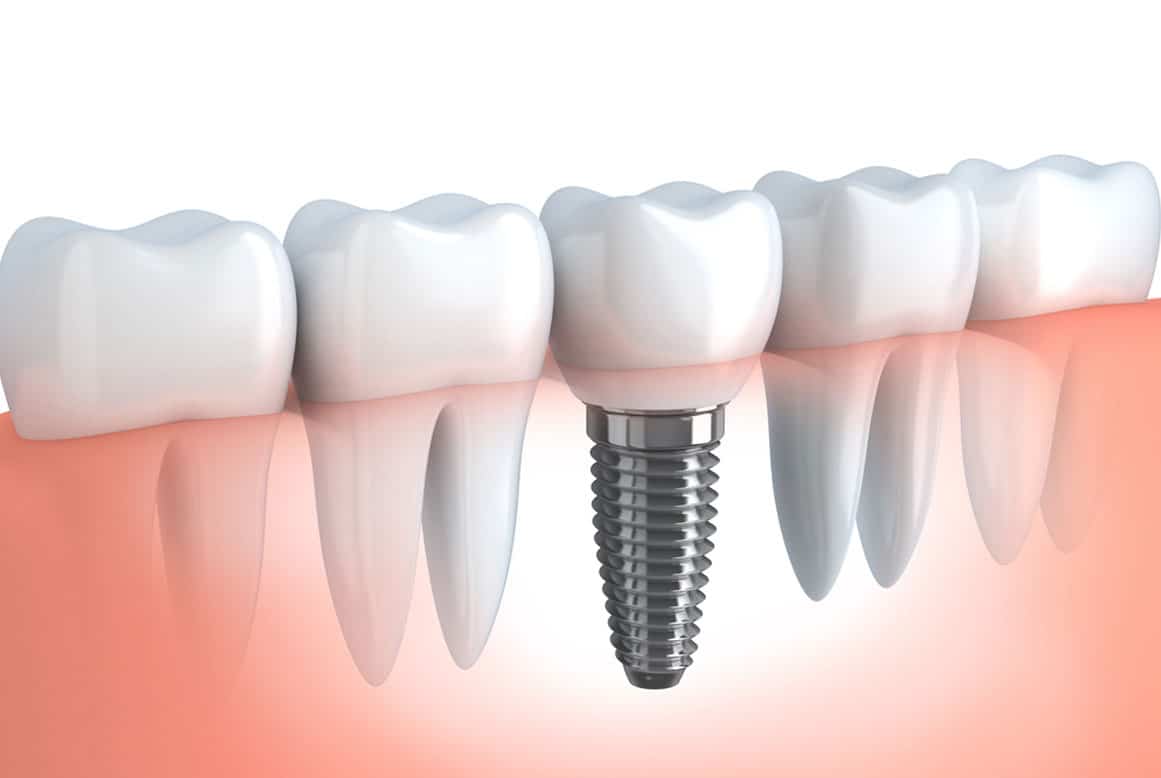

"אין ברירה, צריך לעקור" הן ארבע מילים שמעוררות פחדים עמוקים בחלקים גדולים מדי של האוכלוסייה. עם זאת, לשמחתנו הרבה, בעולם הטכנולוגי המתקדם שבו אנחנו חיים, הזיכרון של טיפולי שיניים כואבים הוא נחלת העבר ולשם עליו לחזור. היום, כל טיפולי השיניים אינם כואבים כל עוד הם מבוצעים בידיים מנוסות ומקצועיות. אם כן, משהפגנו מעט את החששות […]

- 25 שנות נסיון בהשתלת שיניים